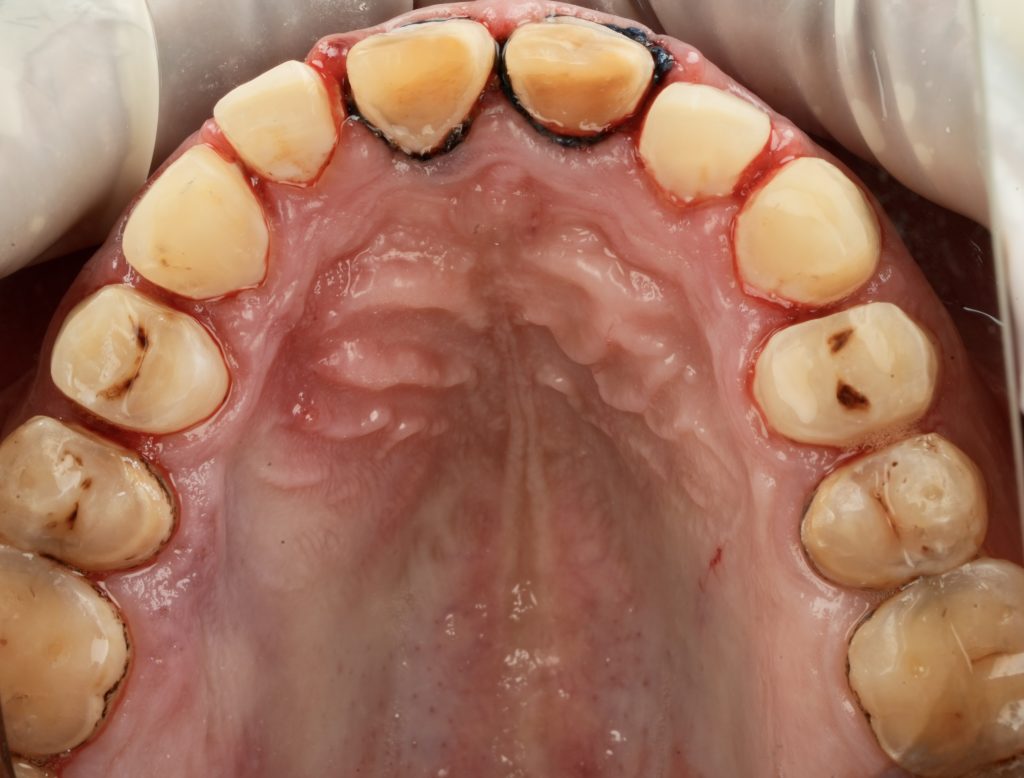

4️⃣ Laboratory Fabrication

IPS E-max Press veneers were pressed and characterized using micro-layered incisal ceramics for vitality and translucency. Surface texture and internal effects were customized to simulate natural perikymata and halo zones (Fig 3).